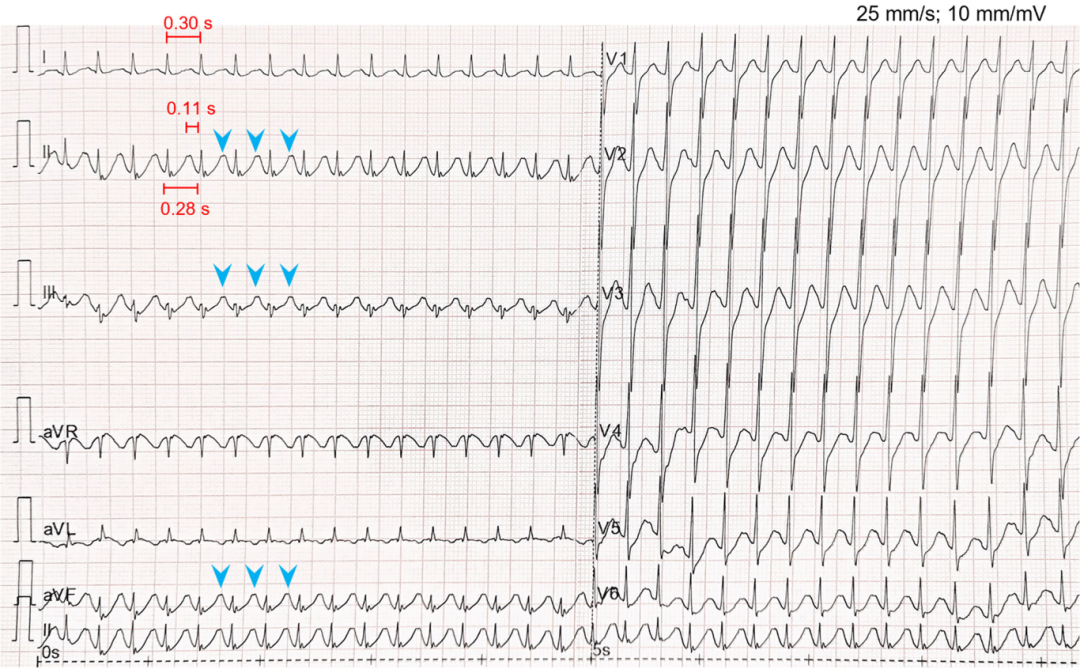

图2 后续12导联心电图显示窄QRS波心动过速(202次/分钟)。在II、III和aVF导联可见ST段压低。注意T波可见切迹(蓝色箭头),提示重叠P波。PR间期为110ms。测量到的QT间期为0.28秒,按Fridericia公式校正后QTc为420ms。

图3 心率下降初期(194次/分钟)以50mm/s的走纸速度记录的心电图。较快的走纸速度使肢体导联中P波形态显示更为清晰。测量的QT间期为0.28s,按Fridericia 公式校正后QTc为416ms。